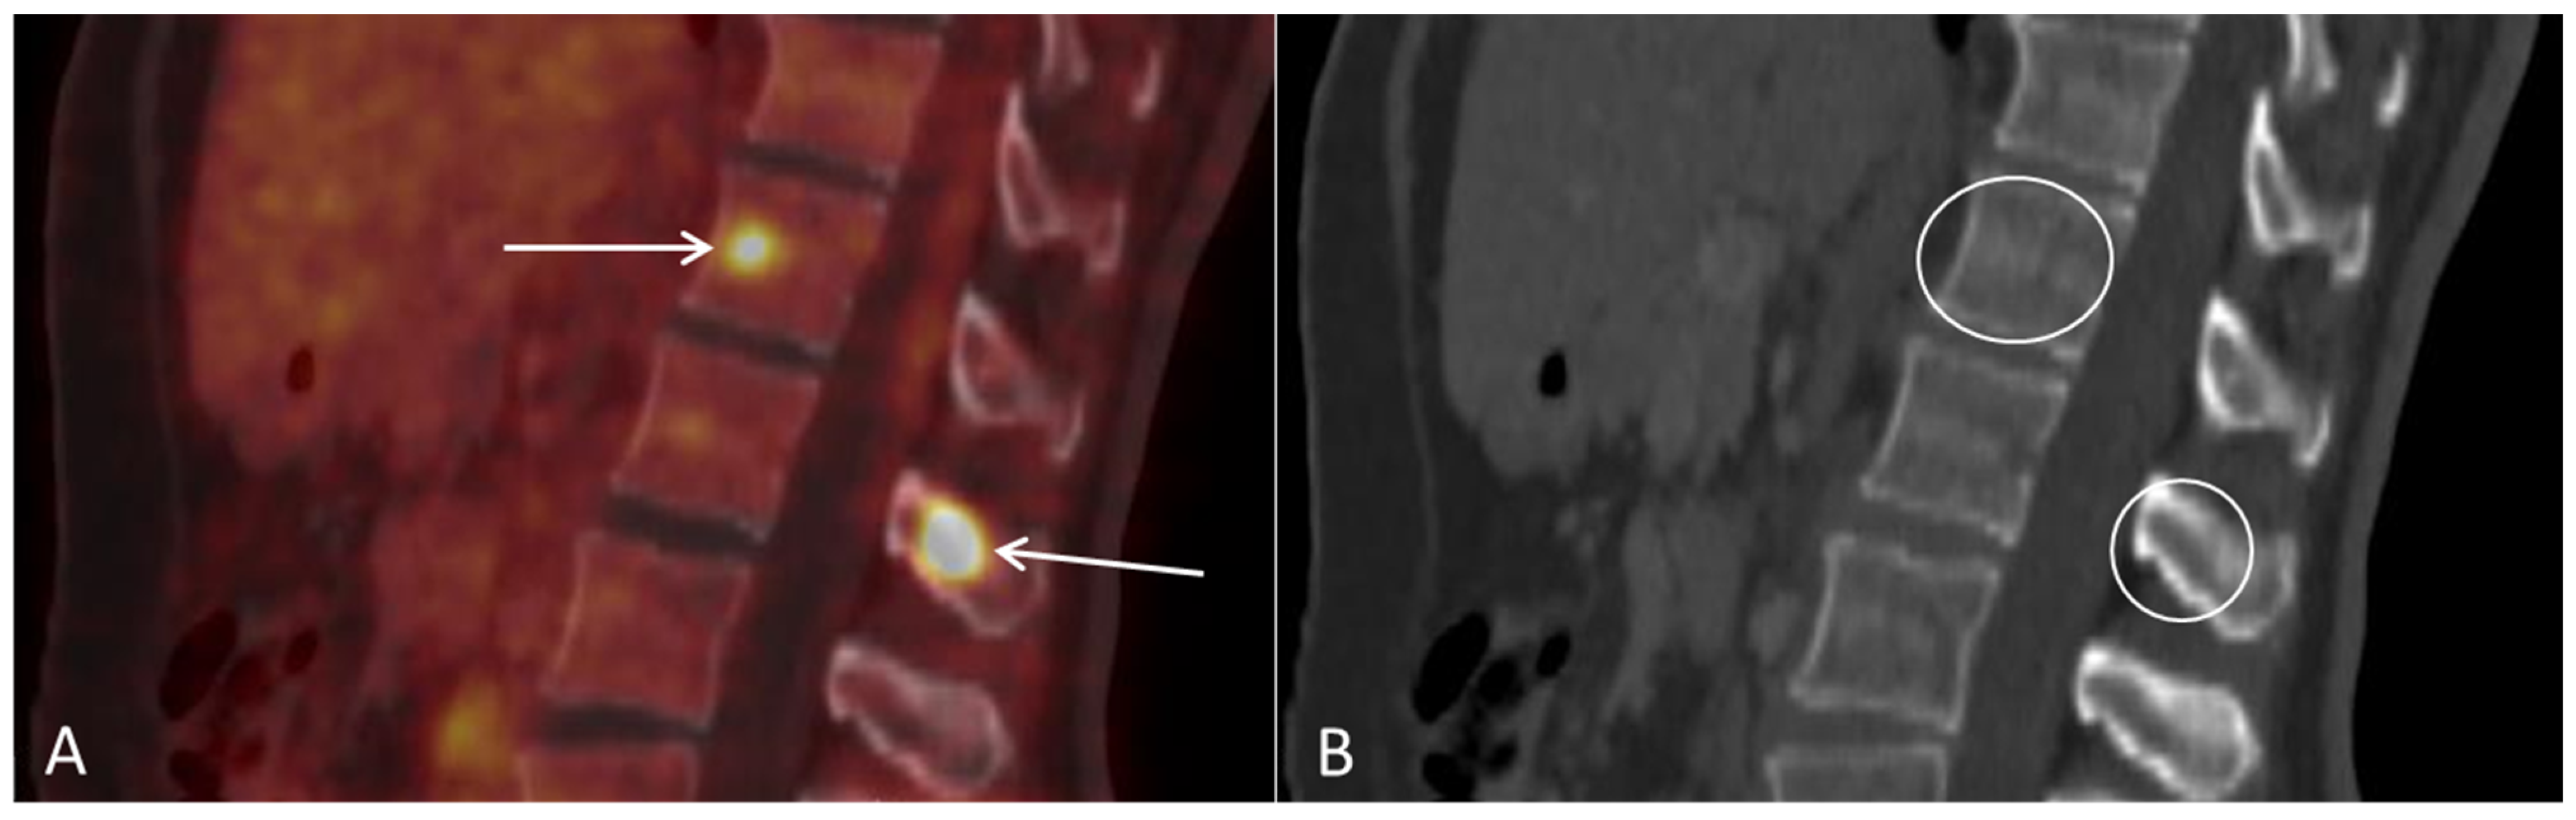

Disseminated Primary Uterine Hepatoid Adenocarcinoma with α-Fetoprotein Production Demonstrated on 18F-FDG PET/CT

Dejanovic, D.; Boennelycke, M.; Amtoft, A.G.; Christensen, C.B.; Wetterstroem, V.; Loft, A.; Noettrup, T.J. Disseminated Primary Uterine Hepatoid Adenocarcinoma with α-Fetoprotein Production Demonstrated on 18F-FDG PET/CT. Diagnostics 2022, 12, 1447. https://doi.org/10.3390/diagnostics12061447